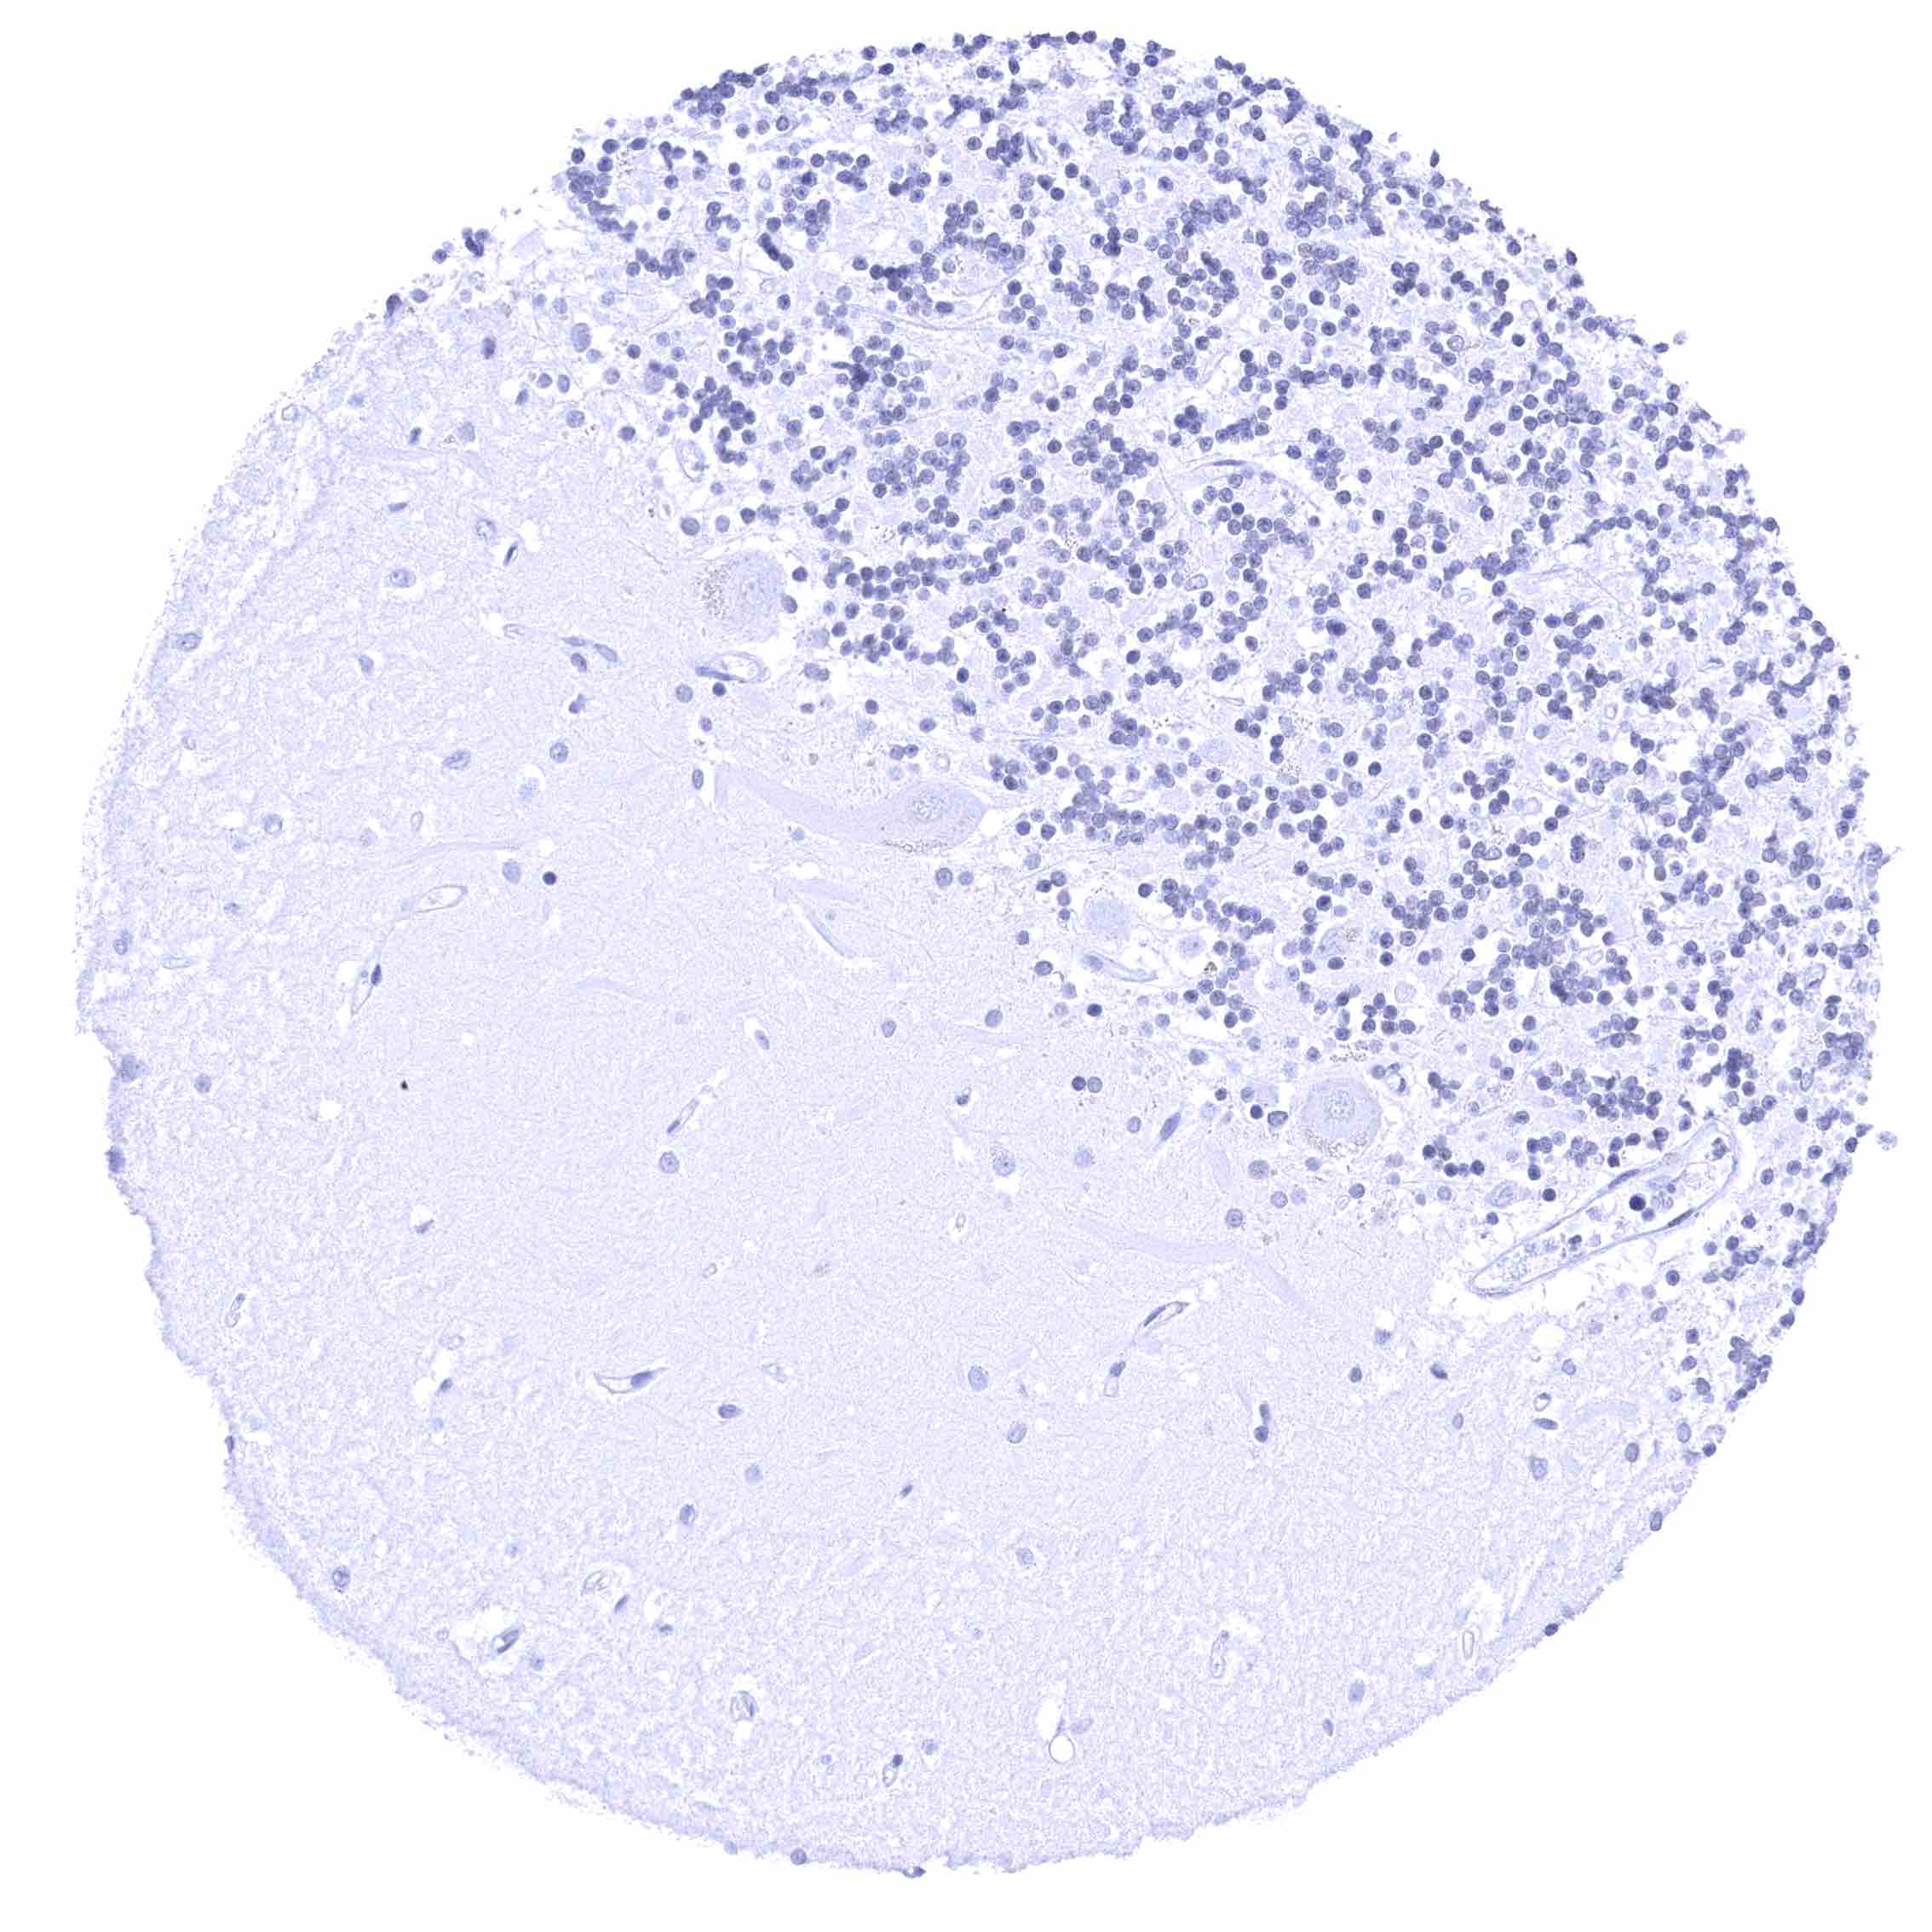

Thymus – Membranous CD70 staining of variable intensity in a small subset of cells.